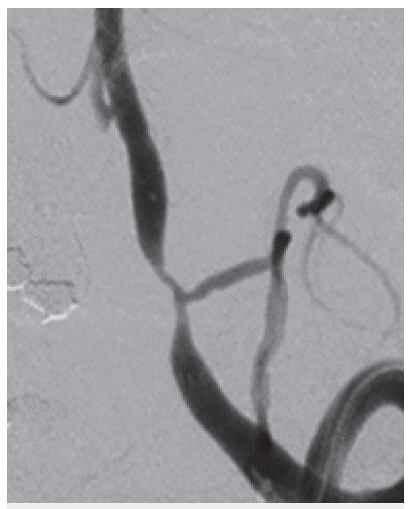

Estenosis de la arteria vertebral izquierda en origen de la arteria cerebelosa posteroinferior

Figura 1: Estenosis de la arteria vertebral izquierda en origen de la arteria cerebelosa posteroinferior